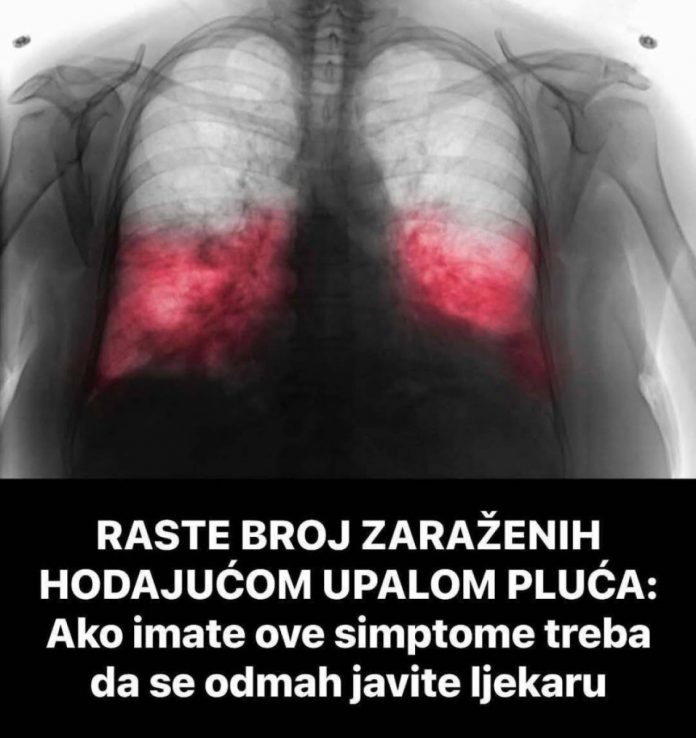

Kada postoji sumnja na hodajuću upalu pluća, ljekar će najprije razgovarati s pacijentom o simptomima i pažljivo poslušati pluća. U mnogim slučajevima potrebne su dodatne analize kako bi se potvrdila dijagnoza.

- To može uključivati laboratorijske nalaze, briseve respiratornih puteva ili rendgenski snimak pluća. Tačna dijagnoza je veoma važna, jer uzročnik ove bolesti često ne reaguje na uobičajene antibiotike koji se koriste kod drugih infekcija.